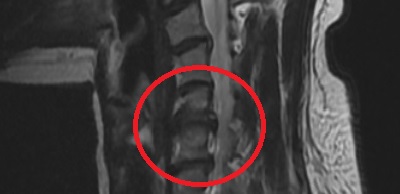

허리디스크에 의해 압박을 받고 있는 신경주위로 유착을 분리시키는 것을 말합니다.

꼬리뼈를 통해 유착된 부위를 확인하고 유착 방지제를 주입하여 증상을 완화시키는 것입니다.

수핵탈출증